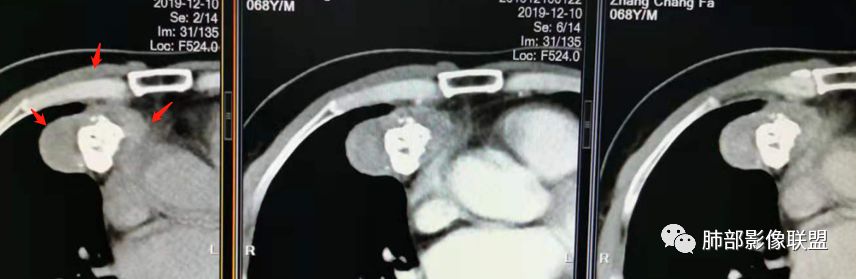

三个石头:前纵隔占位,不规则分叶肿块,内斑片状,点状钙化,内乳动脉增粗,肿块延迟强化。考虑良性占位,疾病谱畸胎瘤,胸腺瘤,巨淋。

右侧前纵膈肿块,边缘分叶,病灶中心可见斑块状钙化,实性成分明显持续强化,考虑胸腺瘤。

弹指之间:定位:1.非肺内来源,2.纵隔或胸膜来源;内乳动脉增粗,cor示与胸膜关系密切;

定性:特点是粗大钙化,延迟强化;首先排除畸胎瘤(无脂肪、有延迟强化);胸腺肿瘤的粗大钙化罕见;综合:SFT>胸腺瘤(高危)。

实性部分密度与肌肉类似,钙化粗大、结节状

右侧内乳动脉增粗

实性部分中度强化——增加20~27HU

深分叶,边界尚清,附近未见肿大淋巴结